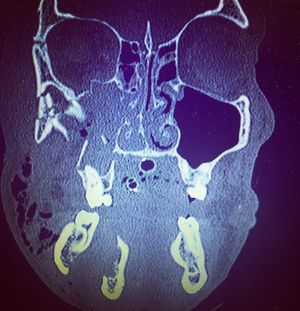

Can you spot the fractures ? 😉This is a coronal slice of a CT scan, meaning you are looking straight at the patient from a face to face point of view ⬆️ This orientation is helpful for examining the bones of the orbits, the sinuses, the cheek bones, as well as my favorite.